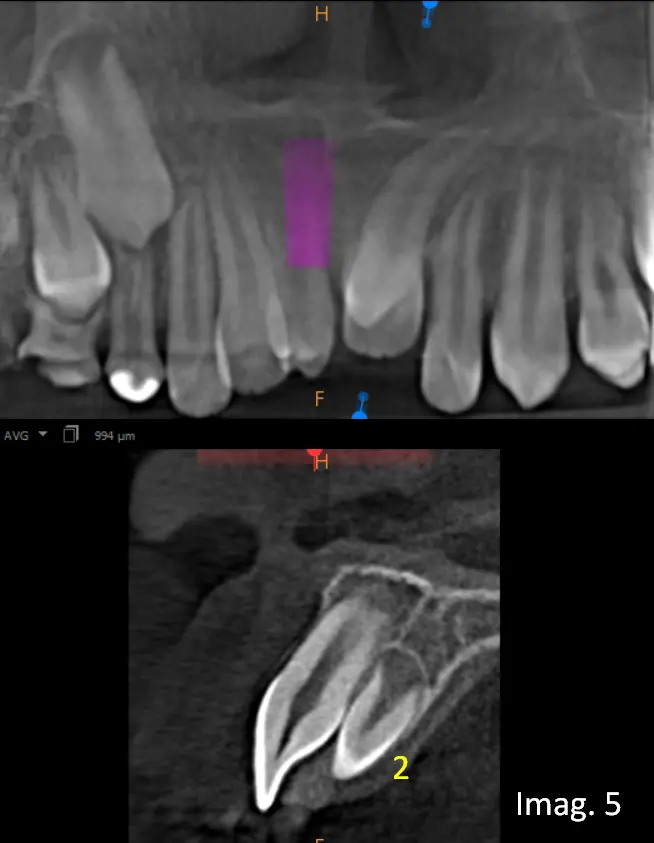

En los cortes transaxiales (imágenes 4 y 5) se visualiza el primer Mesiodens ubicado en posición vestibular, próximo al reborde alveolar, clínicamente erupcionado, mientras que el segundo Mesiodens se encuentra localizado en posición palatina, intraóseo, no erupcionado, en íntima relación con las raíces de los incisivos centrales superiores.